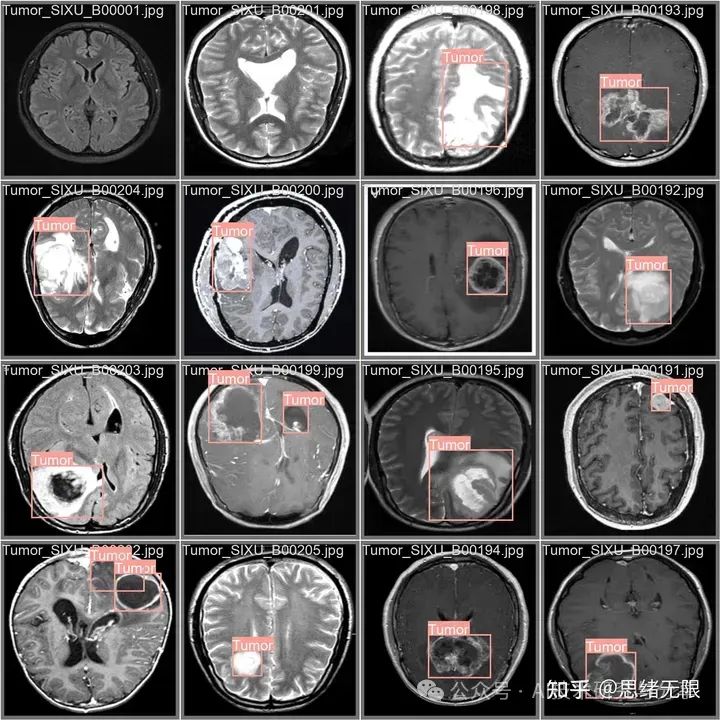

在本研究中,我们专门为训练和评估基于YOLOv8算法的癌症图像检测模型而设计,包含了3076张图像,其中包括2634张用于训练的图像、301张用于验证的图像,以及141张用于测试的图像。这一细致的分配确保了模型能够在足够大的数据集上进行训练,同时拥有独立的测试集和验证集,以评估模型的性能和泛化能力。

在数据预处理方面,我们采取了一系列标准化步骤来确保数据集的一致性和可用性。所有图像均经过自动方向调整处理,确保了图像方向的统一性,并去除了EXIF方向信息,消除了由于拍摄角度不同可能带来的变量。此外,考虑到YOLOv8算法的输入要求,所有图像均被调整至416x416像素的尺寸。这种统一的尺寸不仅有利于算法处理,也有助于减少模型训练和推断过程中的计算开销。

通过对数据集标签的分析,我们发现了一些关键的特征。数据集的实例主要分为两大类:良性和恶性肿瘤。在实例数量上,恶性肿瘤的数量远超过良性,这可能是因为研究的重点是更有效地检测癌症。然而,这种不平衡的分布也提示我们,在训练过程中可能需要使用特定的技术来解决类别不平衡的问题,如调整类别权重或应用过采样技术。

进一步分析边界框的大小和分布,我们发现恶性肿瘤的边界框在大小上相对一致,而良性肿瘤的边界框则呈现出较大的变异性。这可能意味着恶性肿瘤在成像上表现出较为规律的形状和尺寸,而良性肿瘤则在形态上更加多样。这一发现对于设计模型的检测窗口和锚框策略至关重要。

边界框的空间分布分析揭示了数据集中的实例在图像内的分布均匀,这有助于模型学习到在不同位置检测肿瘤的能力。同时,边界框的宽度和高度分布显示出大部分肿瘤在图像中占据较小的区域,这对于设置检测模型的分辨率和感受野具有指导意义。博主使用的类别代码如下:

Chinese_name = {'Benign': "良性", 'Tumor': '肿瘤'}

总之,我们介绍的数据集经过精心设计和预处理,以适应癌症图像检测模型的需求。数据集的类别分布、边界框的大小和形状、以及空间位置的多样性,都是在设计和训练YOLOv8模型时必须要考虑的因素。通过充分利用这些特性,我们能够提高模型的泛化能力和检测精度,进一步推动癌症检测领域的研究和应用发展。